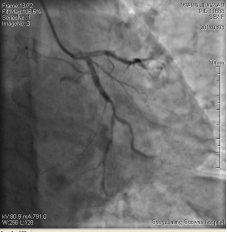

3月3日14時30分:經(jīng)右橈動脈行冠脈造影見:左主干未見明顯異常,TIMI血流3級,前降支開口正常,近中段20%狹窄,TIMI血流3級;回旋支開口正常,中遠(yuǎn)段75%狹窄,TIMI血流3級。右冠狀動脈開口正常,中段長病變,最重99%狹窄, TIMI血流3級。

圖1 回旋支遠(yuǎn)段70%狹窄 圖2 右冠脈中段99%狹窄

中日聯(lián)誼閆明洲教授向家屬交代病情及介入相關(guān)并發(fā)癥后,患者及家屬同意冠脈支架治療,過程順利,于右冠脈中段植入Firebird2 2.5*33mm 藥物洗脫支架1枚。

術(shù)前 術(shù)后